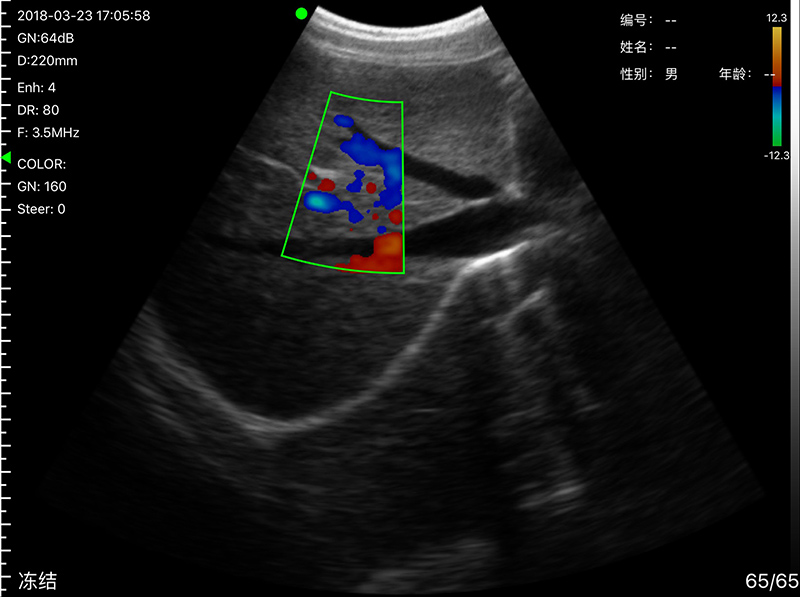

• Probe Head: R60 Convex+R13 Transvaginal

• Display mode: B, B/M, color doppler version with B+Color, B+PDI, B+PW

Convex head 3.2MHz/5MHz, 90/160/220/305mm, R60